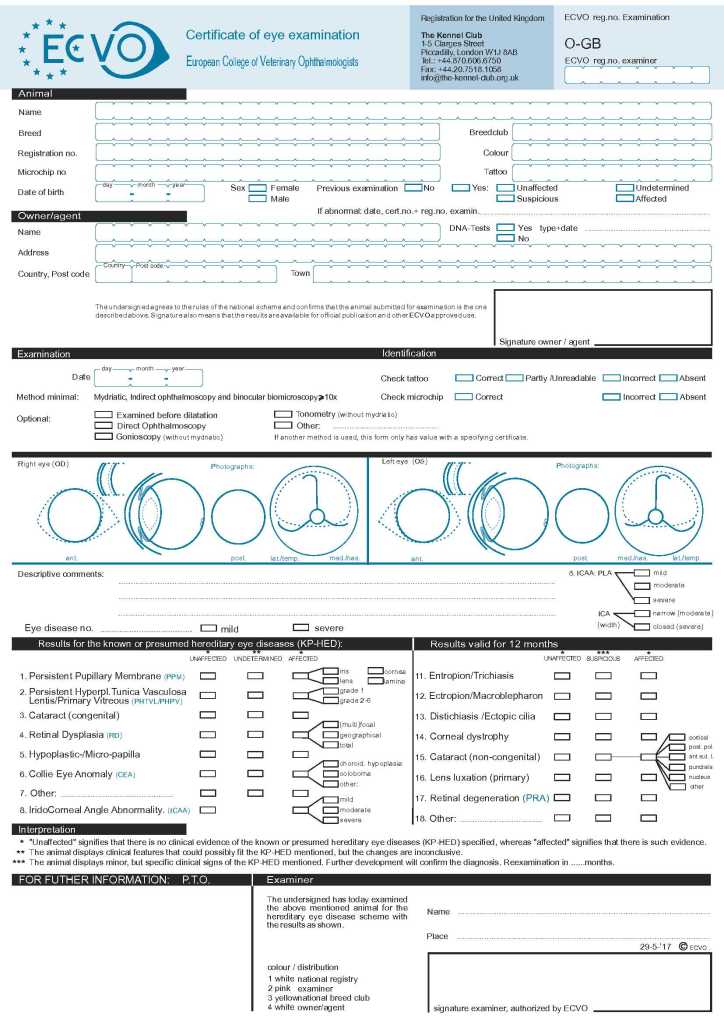

ECVO (European College of Veterinary)

Wat is ECVO?

ECVO staat voor European College of Veterinary Ophthalmologists, de Europese organisatie voor dierenoogspecialisten. Dit onderzoek wordt gebruikt om erfelijke oogafwijkingen op te sporen en ouderdieren te screenen op oogaandoeningen.

Wat wordt er gedaan tijdens het ECVO onderzoek?

Het ECVO-oogonderzoek is een specialistisch oogonderzoek voor honden, uitgevoerd door een erkende dierenoogarts (ECVO-gespecialiseerd). Het ECVO-oogonderzoek controleert dus op erfelijke en andere afwijkingen aan het oog.

Tijdens het onderzoek wordt er gekeken naar de volgende 15 afwijkingen:

- Membrana pupillaris Persistens MMP

- Persisterende hyperplastische tunica vasculosa lentis/primair vitreum (PHTVL/PHPV)

- Cataract (Congenitaal)

- Retina (netvlies) degeneratie

- Hypoplasie / Micropapilla

- Colly eye Anomaly (CEA)

- Ligamentum pectinatum abnormaliteit

- Entropion/ Trichiasis

- Ectropion/ Mecroblepharon

- Distichiasis/Ectopische Cilie

- Cornea Dystrophie

- Cataract (Niet Congenitaal)

- Lens Luxatie (primair)

- Retina Degeneratie (PRA)

Wat betekent dit tijdens het fokken?

Zowel reuen als teven die ingezet worden tijdens de fok, moeten een ECVO onderzoek ondergaan. Dit onderzoek moet door een door het Raad van Beheer aangewezen dierenoogspecialisten gebeuren en mag op de dag van de dekking niet ouder zijn dan twaalf (12) maanden. Dit omdat bepaalde oogziektes pas later tot uiting kunnen komen, een hond die met vier jaar geen opmerkbare oogafwijking heeft, kan die met vijf jaar bijvoorbeeld wel hebben. De ASCN zegt het volgende in hun fokregelement omtrent het ECVO onderzoek:

“Alleen geldig zijn de oogonderzoeksresultaten van bij de ECVO of ACVO aangesloten ophthalmologisten (zie ecvo.eu of acvo.org).

Van ouderdieren waarvan de eigenaren in het buitenland wonen wordt een vergelijkbare uitslag van een door de FCI erkende kennelclub aangewezen instantie geaccepteerd.

Alle ouderdieren beschikken over een geldende ooguitslag (niet ouder dan 12 maanden op de dag van de dekking).

De uitslag dient op alle afwijkingen “vrij” te zijn met uitzondering van:

– MPP iris-iris

– Ouderdomscataract (vastgesteld door de onderzoeker)

– Distichiasis*

*“een ouderdier met een ECVO-ooguitslag “distichiasis, gradatie ernstig (severe)” mag niet ingezet worden voor de fokkerij.

*“een ouderdier met een ECVO-ooguitslag “distichiasis niet-vrij” mag worden gecombineerd met een vrije partner”.” (ASCN FVK, 2022)